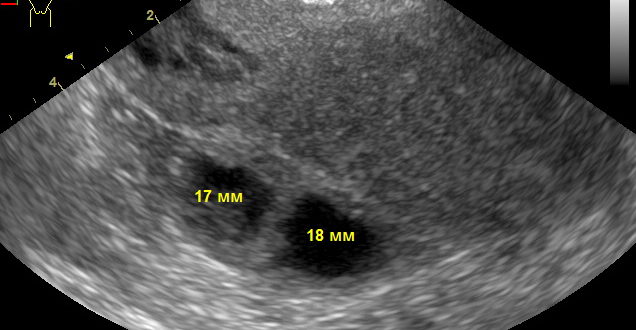

Могли ли перепутать миому с желтым телом?

Методы диагностики миомы матки В пятерку самых распространенных заболеваний женской половой системы входит миома матки. Это доброкачественное образование, которое появляется чаще всего у женщин за 40, но молодые…